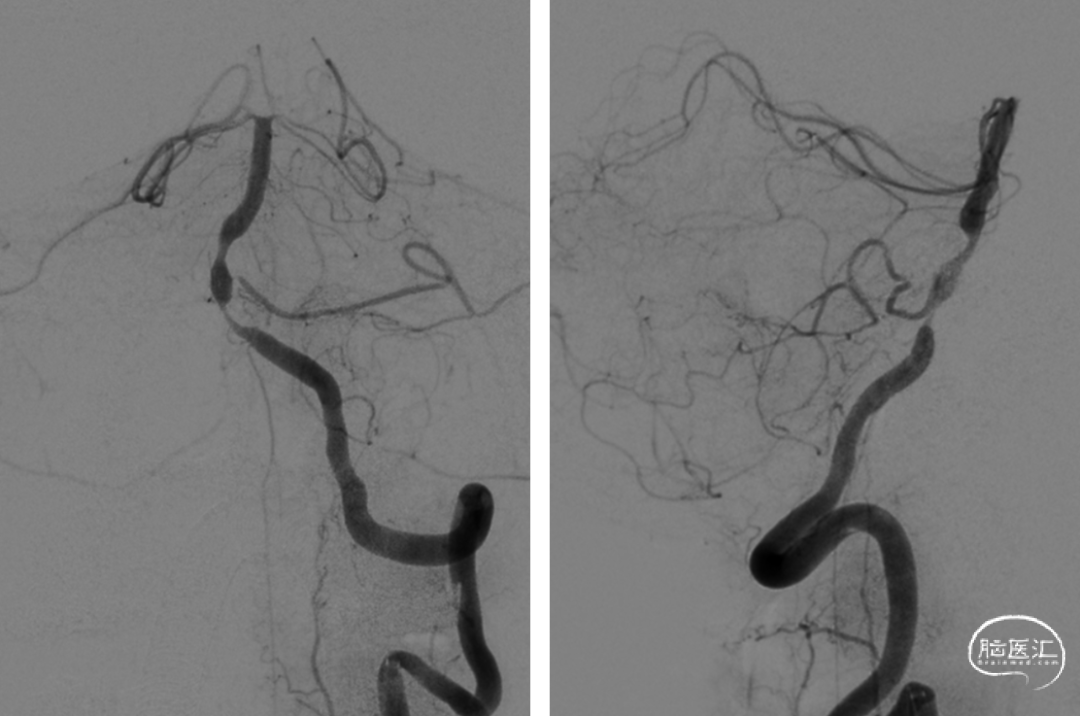

微导丝置于右侧小脑上动脉,导引Fastunnel®通过狭窄。

分别对近端狭窄及远端狭窄进行扩张。

扩张后造影,狭窄较前明显改善,右侧大脑后动脉显影。

沿球囊送入NeuroStellar® 4.5mm*30mm颅内支架一枚,定位准确后释放支架。

术后即刻造影支架位置良好,支架内管腔通畅,远端双侧大脑后动脉均可显影,残余狭窄率<10%,Vaso-CT可见支架打开良好。麻醉清醒后无新发神经功能缺损症状及体征。

左右滑动切换图片